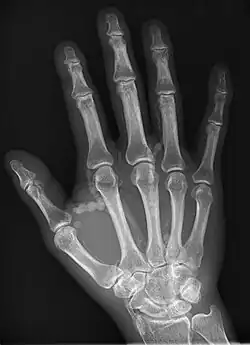

Hand radiograph showing tumoral calcinosis, PA radiograph of the right hand showing tumoral calcinosis-like metastatic calcification in a patient on dialysis. Dialysis alters calcium phosphate product (>70). Idiopathic tumoral calcinosis is autosomal dominant and is not associated with dialysis. Note the premature arterial calcification which is a clue that this is a renal patient. Vascular calcification contributes to an increase in morbidity.

Tumoral calcinosis is a rare condition in which there is calcium deposition in the soft tissue in periarticular location, around joints, outside the joint capsule.[1] They are frequently (0.5–3%) seen in patients undergoing renal dialysis. Clinically also known as hyperphosphatemic familial tumoral calcinosis (HFTC), is often caused by genetic mutations in genes that regulate phosphate physiology in the body (leading to too much phosphate (hyperphosphatemia)). Best described genes that harbour mutations in humans are FGF-23,[2] Klotho (KL),[3] or GALNT3.[4] A zebrafish animal model with reduced GALNT3 expression also showed HFTC-like phenotype,[5] indicating an evolutionary conserved mechanism that is involved in developing tumoral calcinosis.

The name indicates calcinosis (calcium deposition) which resembles tumor (like a new growth). They are not true neoplasms – they don't have dividing cells. They are just deposition of inorganic calcium with serum exudate. Children and adolescents (6 to 25 years) are the most commonly affected. The symptom that the accumulations cause is not pain but swelling around joints. They have propensity to enlarge progressively and ulcerate the overlying skin and extrude. They are most common around shoulders, hips and elbows. Laboratory evaluation reveal normal serum calcium levels and hyperphosphatemia. Rarely ALP (alkaline phosphatase – an enzyme active at sites of bone formation) may be elevated. Treatment is normalization of serum phosphate levels and resection of lesions. Surgical removal should be complete and if part of it is left, recurrence is likely to occur. Cutting through the excised calcium deposition reveals semifluid calcium suspension in albumin encapsulated by fibrous tissue.